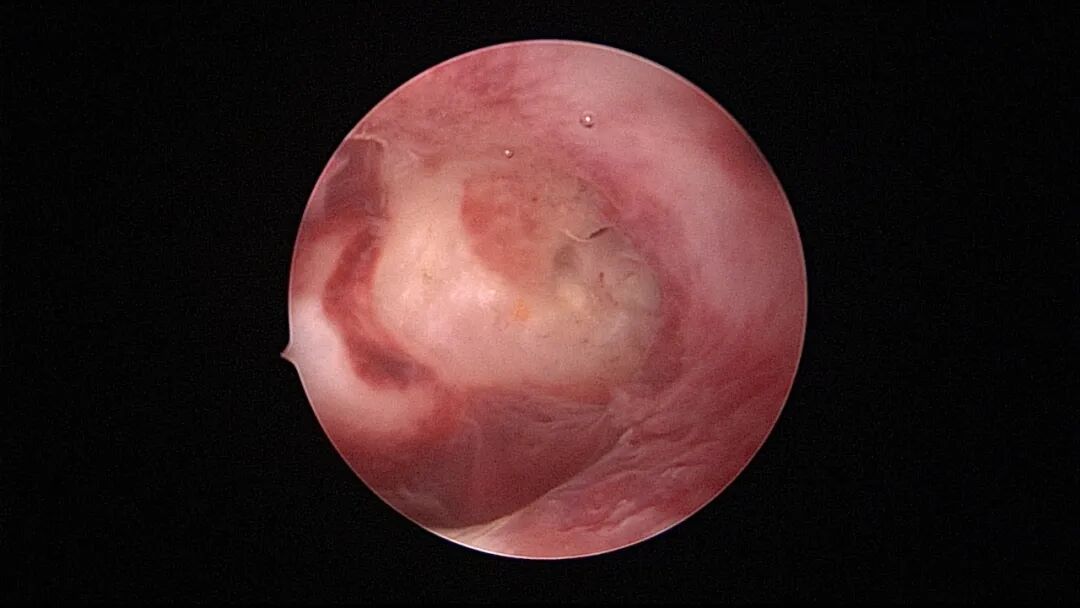

第七次宫腔镜:2025年6月因异常子宫出血、月经淋漓不净10+天,行宫腔镜探查,宫颈管见陈旧血丝,宫腔形态欠规则,宫腔两侧纤维性粘连,宫腔狭小,内膜薄,内膜充血。单极电针分粘,宫腔形态基本恢复正常,左侧输卵管开口显露,右侧输卵管开口不可见。内膜病检为增殖期样子宫内膜伴出血。